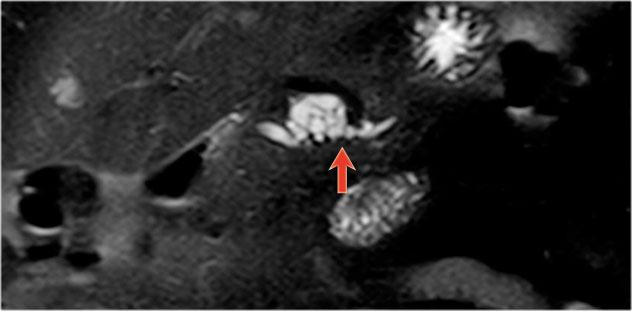

Một trường hợp IPMN thể ống nhánh khác phát hiện qua tầm soát với hai nốt (vòng tròn và mũi tên).

Chuỗi xung T1W xóa mỡ trước (hình bên trái) và sau tiêm thuốc tương phản từ (hình bên phải).

Siêu âm nội soi (EUS) có thuốc tương phản từ cho thấy 2 ổ không ngấm thuốc, nhiều khả năng là nút nhầy.

Sau 6 năm theo dõi, nang không thay đổi.

Nam giới 75 tuổi với IPMN ống nhánh kích thước 2,7 cm tại đầu tụy (vòng tròn).

Trong quá trình theo dõi một năm sau, phát hiện giãn ống tụy chính.

Siêu âm nội soi (EUS) cho thấy ung thư biểu mô tuyến còn khả năng phẫu thuật cắt bỏ.